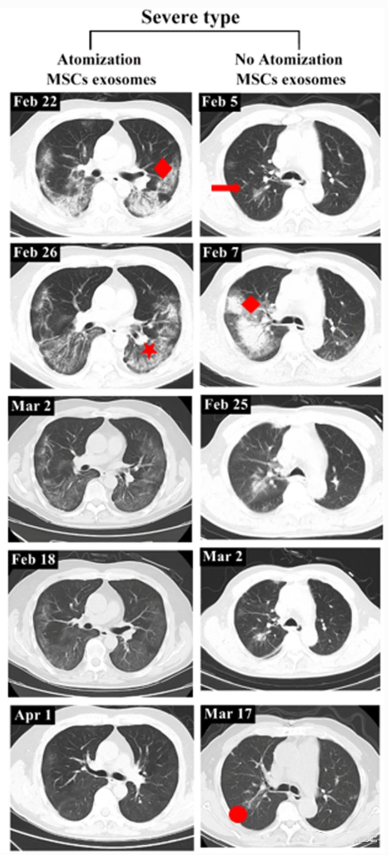

Severe patients recover better after exosome nebulization therapy:

A critically ill patient began exosome nebulization therapy on February 27, 2020, and on March 18, the patient’s CT scan showed significant resorption of both lung lesions and regression of lesion density. On April 1, the patient’s lung lesions were completely absorbed.

In another critically ill patient who did not receive exosome nebulization therapy, fibrous umbilical cord shadow still existed after resorption of lung lesions.

▲Left: Severe cases with exosome nebulization therapy. Right: Severe cases without exosome nebulization therapy